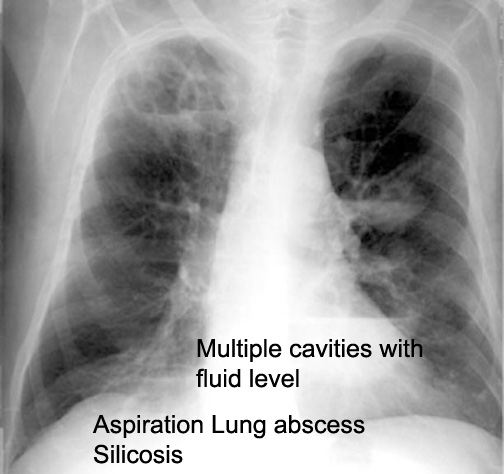

Case 10 Labeled Image What is the differential for multiple cavities?